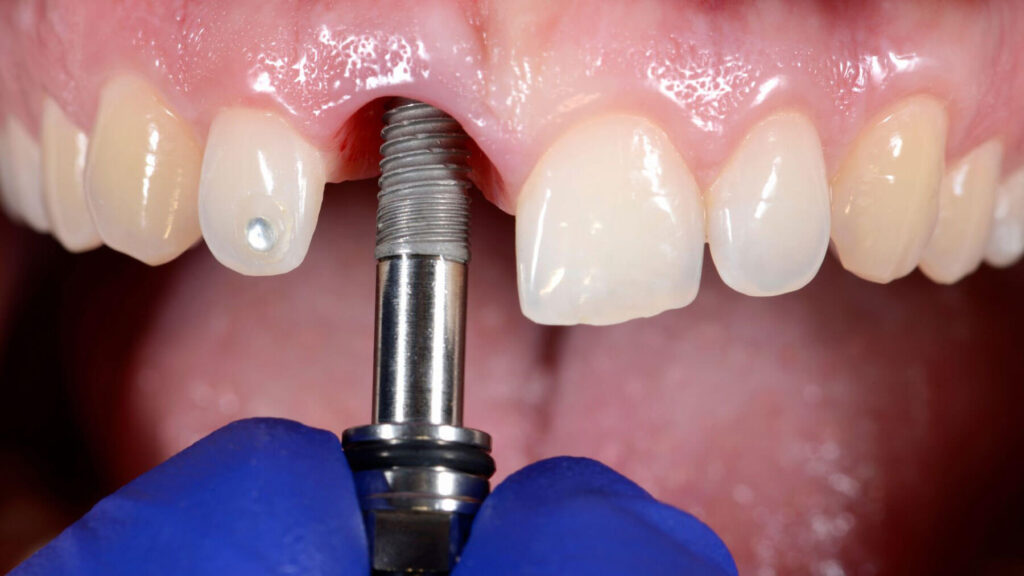

Implant Placement

During the implant placement procedure, the titanium posts are surgically inserted into the jawbone. This step is typically performed under local anesthesia.

Abutment Placement

After healing, the dentist attaches abutments that connect the implant to the final restoration.